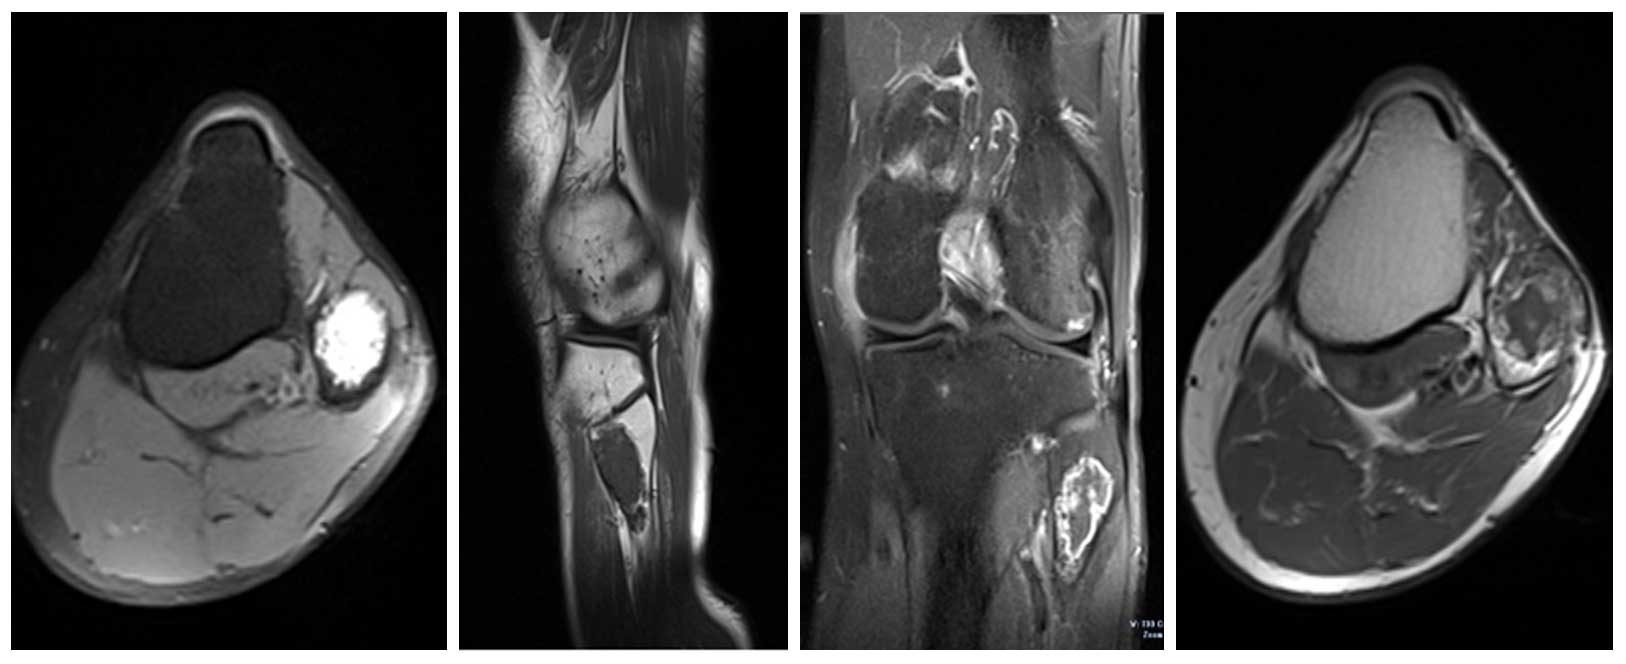

Ameliyat Öncesi: MR’da düzensiz sınırlı, kortekste incelmeye neden olan kitle görülmekte.